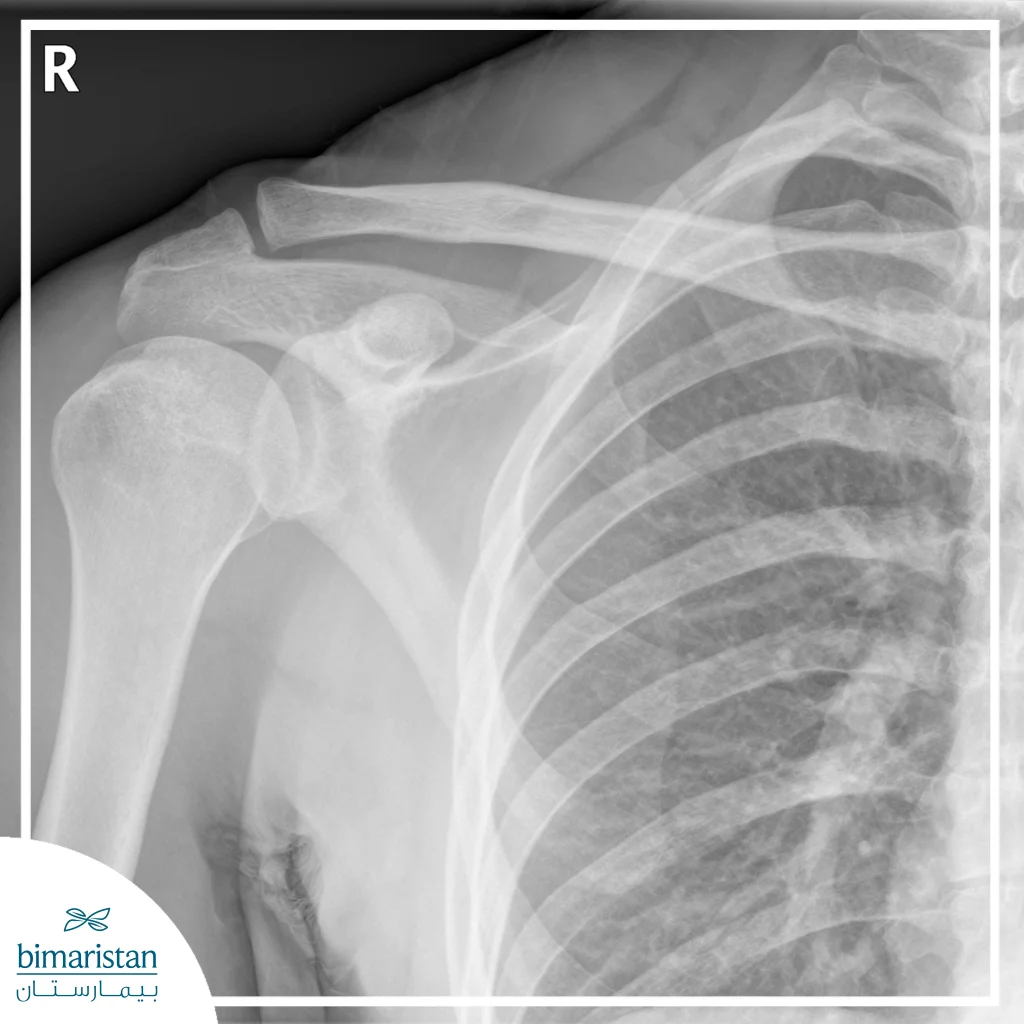

X-rays

X-rays are the most common way to diagnose shoulder fractures, as they show the bones clearly and reveal the location and type of fracture (simple or complex). X-rays help doctors determine the extent of bone displacement and assess the need for surgical stabilization or conservative treatment.